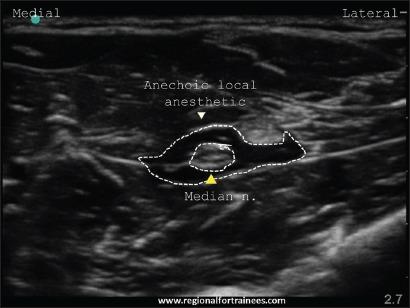

Upper extremity surgery is commonly performed under regional anesthesia. The advent of ultrasonography has made performing upper extremity nerve blocks relatively easy with a high degree of reliability. The proximal approaches to brachial plexus block such as supraclavicular plexus block, infraclavicular plexus block, or the axillary block are favored for the most surgical procedures of distal upper extremity. Ultrasound guidance has however made distal nerve blocks of the upper limb a technically feasible, safe and efficacious option. In recent years, there has thus been a resurgence of distal peripheral nerve blocks to facilitate hand and wrist surgery. In this article, we review the technical aspects of performing the distal blocks of the upper extremity and highlight some of the clinical aspects of their usage.

上肢手术通常在区域麻醉下进行。超声检查的出现使得进行上肢神经阻滞相对容易,且可靠性高。对于大多数上肢远端的外科手术,臂丛神经阻滞的近端入路,如锁骨上神经丛阻滞、锁骨下神经丛阻滞或腋路阻滞,是比较常用的。然而,超声引导使得上肢远端神经阻滞成为一种技术上可行、安全且有效的选择。近年来,远端周围神经阻滞因此再度兴起,以方便手部和腕部手术。在本文中,我们回顾了进行上肢远端阻滞的技术要点,并强调了其使用的一些临床方面。